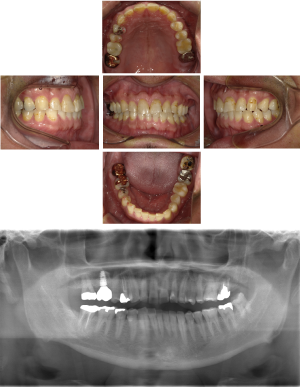

50代 インプラント治療(右上3左上3のみGBR)

| 年代・性別 | 50代・男性 |

| 主訴 | 入れ歯が合わず毎日ヨーグルトしか食べることができないので、しっかり咬めるインプラントにしたい。 |

| 部位 | 右下⑦⑥5④ 上顎③2①①2③ 左下67 |

| 治療期間 | 約9ヶ月 |

| 費用 | ¥4,273,500(税込) |

| 副作用・リスク |

|